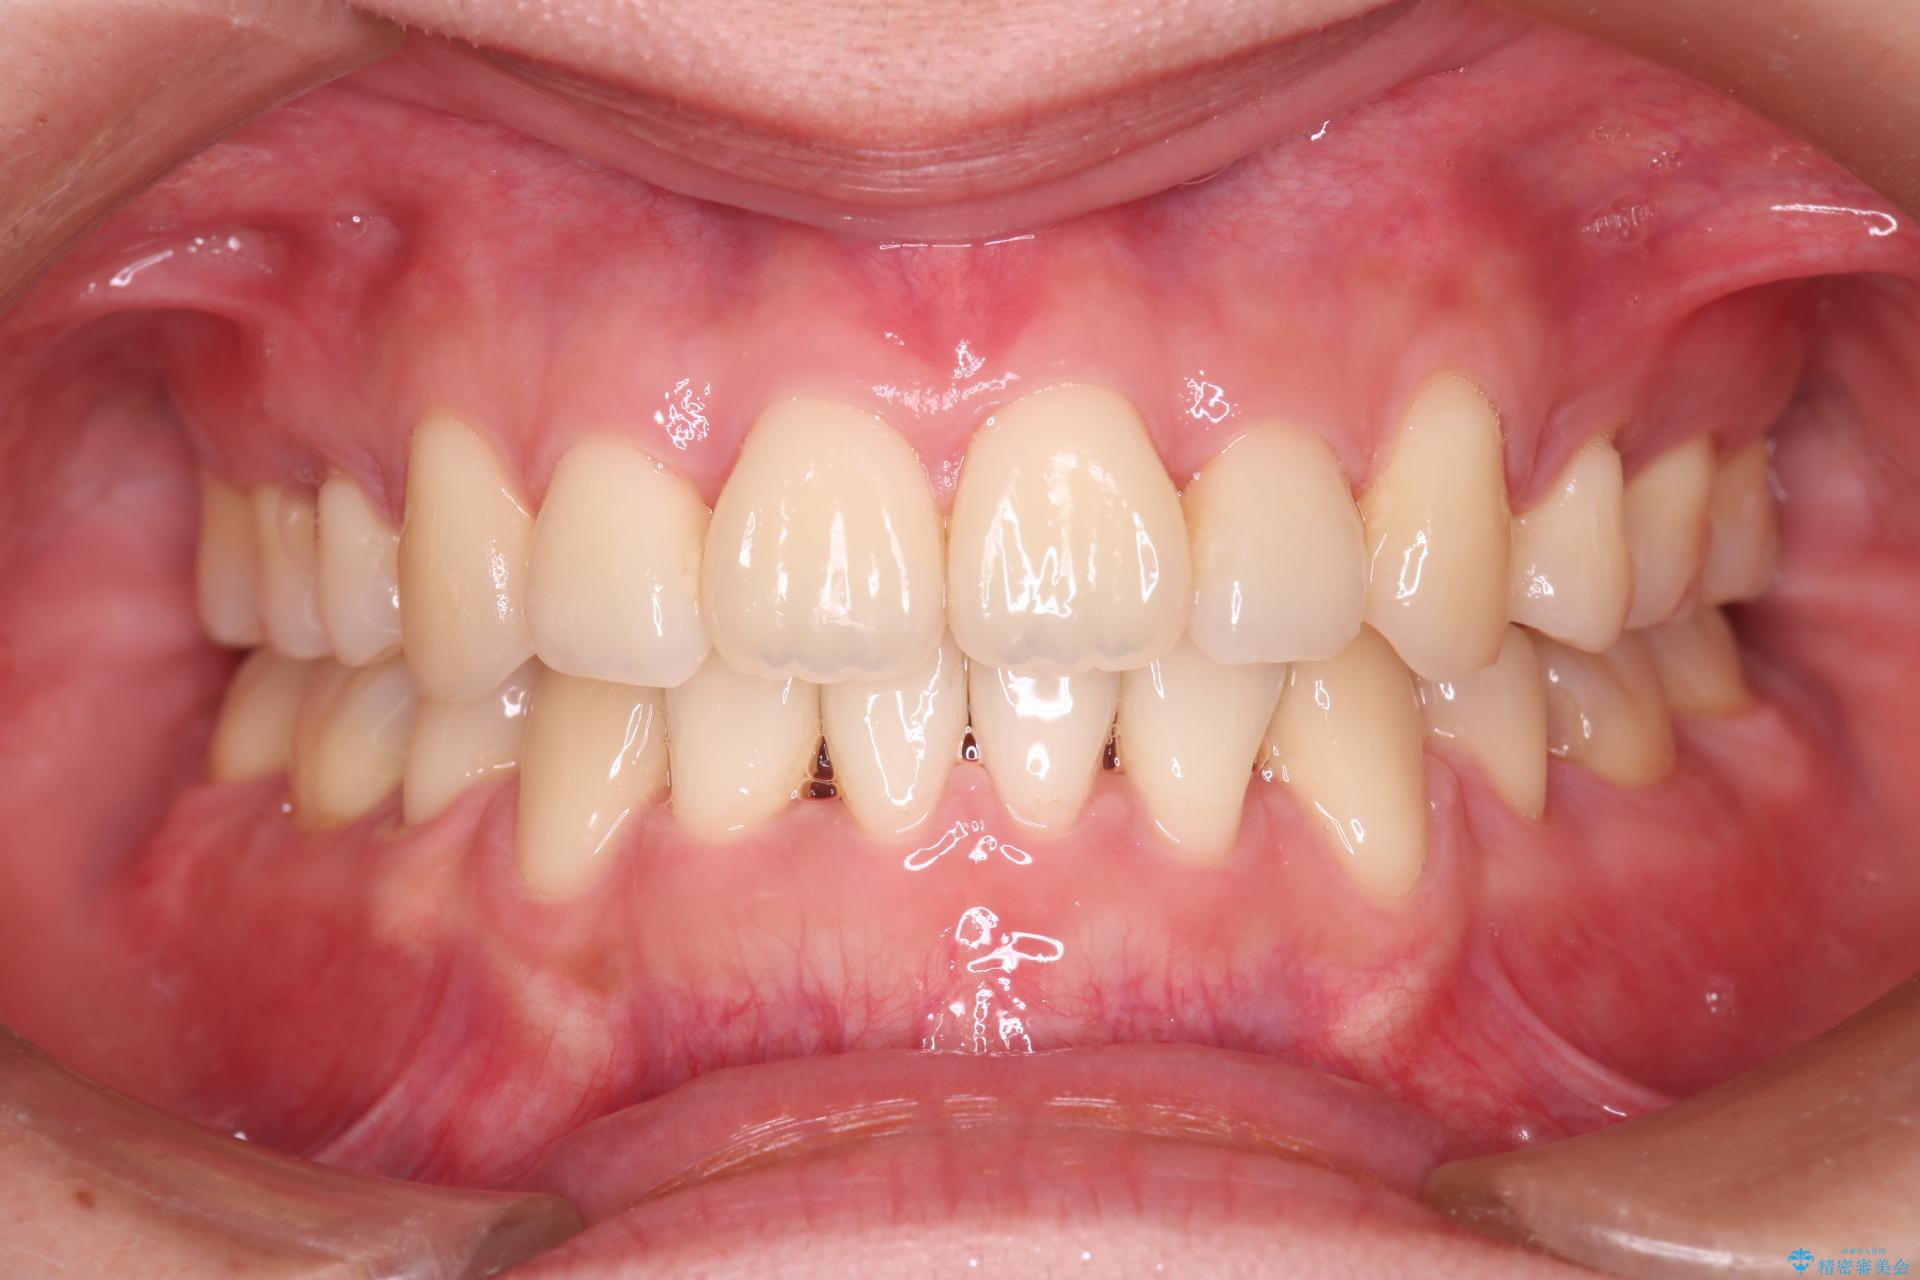

前歯のデコボコが改善され、噛みあわせも綺麗になりました。

歯肉退縮もなく、予定通りに治療を終えることができ大変ご満足いただけました。